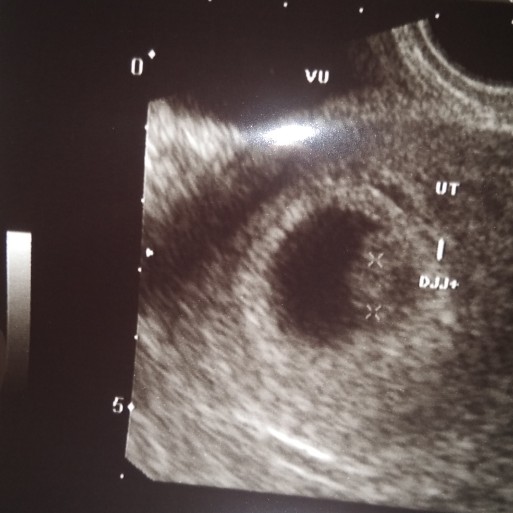

Muncul bercak pada usia kehamilan 6 minggu

Mau tanya dong bunda bunda, aku kan baru hamil anak pertama usia kehamilan ku 6 minggu, nah 4 hari setelah cek ke bidan, kok malam malam keluar flek. Tak lama ku langsung periksa ke bidan malam nya. Di cek ternyata darah nya banyak kata bidan nya di dalam, dan di suruh tespeck lagi sama bidan nya masih positif. Akhirnya di kasih obat penguat kandungan. Tapi bercak darah nya masih ada. Sudah berjalan 3 hari. Darah nya itu cokelat dan merah tua gitu, gasering keluar seperti haid tapi selalu ada di celana ku. Itu kenapa yah kira kira? Ada yg pernah ngalamin gak bunda bunda ??? Aku jadi resah dan khawatir terus